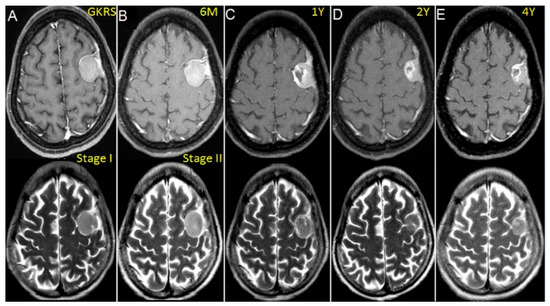

2.2. Treatment Approach and Exposure Variable